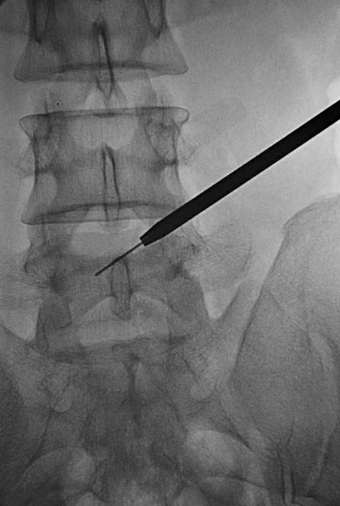

置入2级导杆使头端到达第一靶点(图18)。

图18 置入2级导杆A.前后位透视:头端到达第一靶点;B.侧位透视:侧位透头端抵达L5椎体后上缘。

拔出导丝,将导杆尾端压向腹侧,用手锤敲打导杆尾端,使导杆头端在L5椎体后缘潜行到达第二靶点(图19)。

图19 拔出导丝,将导杆尾端压向腹侧,用手锤敲打导杆尾端,使导杆头端在L5椎体后缘潜行到达第二靶点A.侧位透视头端抵达L5椎体后缘;B.前后位透视头端到达第二靶点。

第二靶点成形:在导丝、2级导杆及2扩张管外,逆时针旋入2级环锯,抵达关节突,进行2级扩孔环锯头端扺达第二靶点(图20)。

图20第二靶点成形,前后位透视:环锯头端抵达第二靶点。

3.第三靶点成形环锯头端不是同轴扺达第三靶点,导杆和扩张管退缩,是危险操作,应避免(图23)。